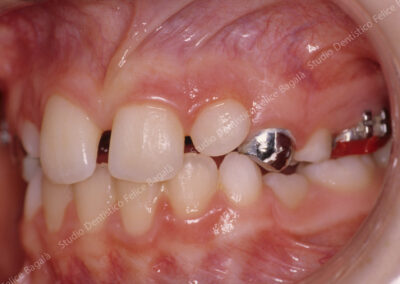

IL CASO DI DANIELE (MORSO CROCIATO)

Daniele 8 anni Morso crociato destro con deviazione mandibolare  e linee mediane dallo stesso lato (vedi frecce nere). Dopo allargamento della parte superiore (mascellare e palato) la mandibola si porta al centro (vedi frecce nere) . Daniele da quel momento continuerà a crescere e sarà controllato periodicamente. Dopo questo breve fase intercettiva di durata di 8/10 mesi non ha avuto più alcun bisogno di ortodonzia. Le deviazioni mandibolari da morso crociato vengono annoverate tra i principali motivi di disturbi muscolo articolari ( Disfunzioni ATM) nell’adulto.

Durante